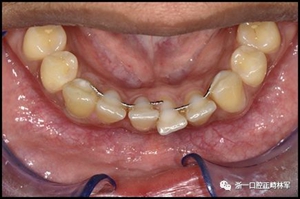

當弓絲斷裂時,由于意外的牙齒移動更可能導致牙齒排列整齊性喪失。這似乎最可能發(fā)生在較小直徑的極軟弓絲上(圖1),但它也會在粘合每顆牙齒的小柔性螺旋弓絲上發(fā)生。弓絲斷裂可能導致根本無法保持當弓絲部分缺失時,或可能導致由剩余弓絲部分造成的個別牙齒移動(圖2)。

圖1.中間切牙間極軟弓絲斷裂,導致2段牙齒移動。注意左側尖牙和左側中切牙的扭矩在相反的方向。

圖2.極軟弓絲,一半缺失,間隙開放和牙齒移動。很可能右側牙齒在最后失去之前被該側的弓絲段移動。